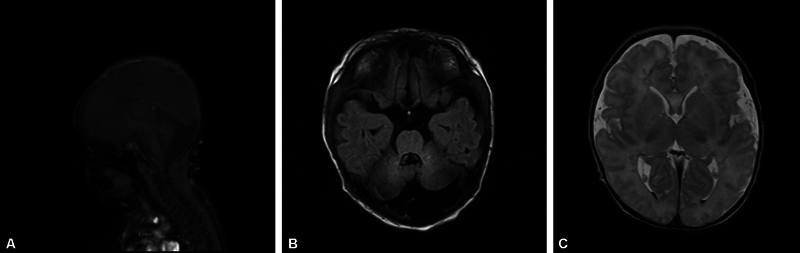

背景:很少有与努南综合征(NS)相关的Dandy-Walker畸形的报道。病例介绍:我们在此提出一个患有Dandy-Walker畸形(DWM)的晚期早产儿的病例,该婴儿接受了喂养困难的检查,并被发现患有NS。这是少数报道的DWM合并NS具有PTPN11基因突变的病例之一。结论:重叠的临床特征可能会掩盖婴儿多重病理的诊断。

Background: There are few reported cases of Dandy-Walker Malformation associated with Noonan syndrome (NS).

Case presentation: We herein present a case of a late preterm infant with Dandy-Walker malformation (DWM) that underwent a workup for feeding difficulty and was found to have NS. This is one of the few reported cases of DWM with NS having a PTPN11 gene mutation.

Conclusion: Overlapping clinical features may disguise diagnosis in infants with multiple pathologies.